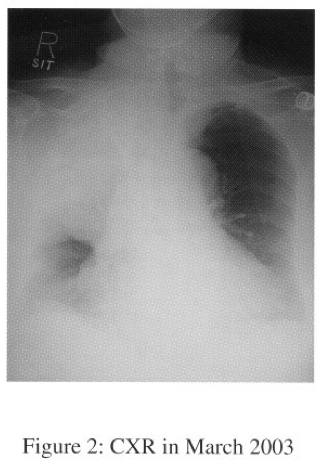

In Sept 2003, she was admitted to NDH for progressive dyspnoea and cough. CXR showed huge right lung opacity with right sided pleural effusion (Serial CXRs shown on figures 1-3).

Chest radiograph is the most important radiological tool for evaluation of SFT. It appears as a well-defined, homogeneous, and rounded mass on CXR. Pedunculated form of SFT has been reported to be moving on successive CXRs. Pleural effusion occurs in 8 – 17%, especially associated with malignant SFT. Calcifications are present in 7% of the tumour.